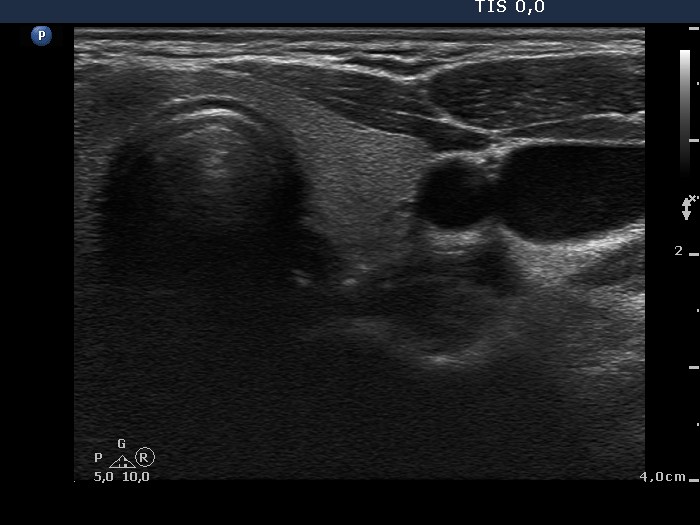

Clinical presentation: A 34-year-old woman was referred for evaluation of a thyroid nodule, which was discovered by the patient herself 3 months ago.

Palpation: a very firm nodule in the right side of the isthmus.

Ultrasonography. The thyroid was echonormal. There was a moderately hypoechogenic nodule in the right side of the isthmus. The ventral part of the lesion was not separated from the sternocleidomastoid muscle. The lesion presented microcalcifications and signs of perilesional blood flow.

Cytology resulted in papillary carcinoma.

A right lobectomy was performed. Histopathology disclosed a T1N0 papillary carcinoma with a maximal diameter of 8 mm.

Comment. Although the tumor did not spread extrathyroidal, even minimal extrathyroidal growth was absent, the ultrasound pattern was highly suspicious of extrathyroidal extension.